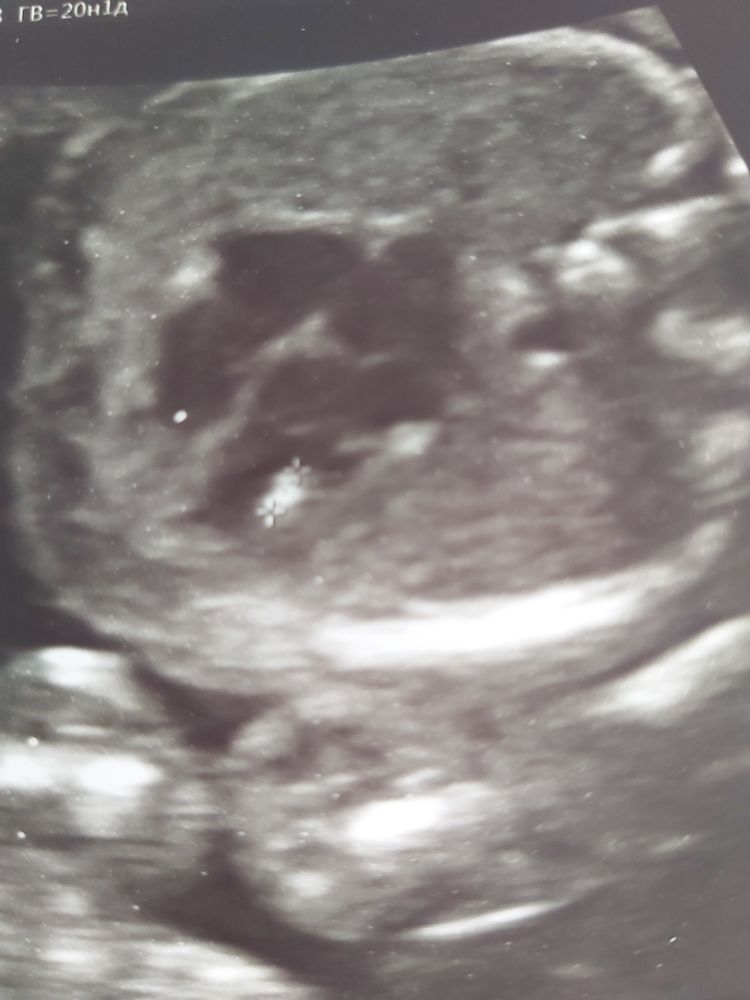

2 скрининг ГЭФ левого желудочка и риски по 1 скринингу.

Есть нипт, он с низкими рисками. Сегодня был 2 скрининг, обнаружили гэф в левом желудочке d 3мм.

Если НИПТ хороший, то не о чем переживать. ГЭФ либо рассосётся, либо, опять же, может стать дополнительной хордой. Тоже не имеет существенного значения.

У меня низкие риски были по крови и тоже был гиперэхогенный фокус в левом желудочке. Врачи всегда спрашивали про биохимию, а когда узнавали, что кровь у меня хорошая, то на этот фокус никто внимания не обращал.